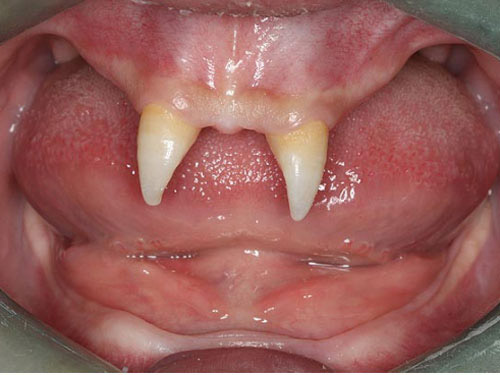

Wang Pengfei, 16 tuổi, sống tại thành phố Trùng Khánh, tây nam Trung Quốc. Sinh ra đã mắc phải một chứng bệnh lạ, Pengfei có rất ít tóc và chỉ mọc duy nhất 2 chiếc răng nhọn hoắt.

Cậu bé Trung Quốc có hàm răng phát triển lạ kỳ